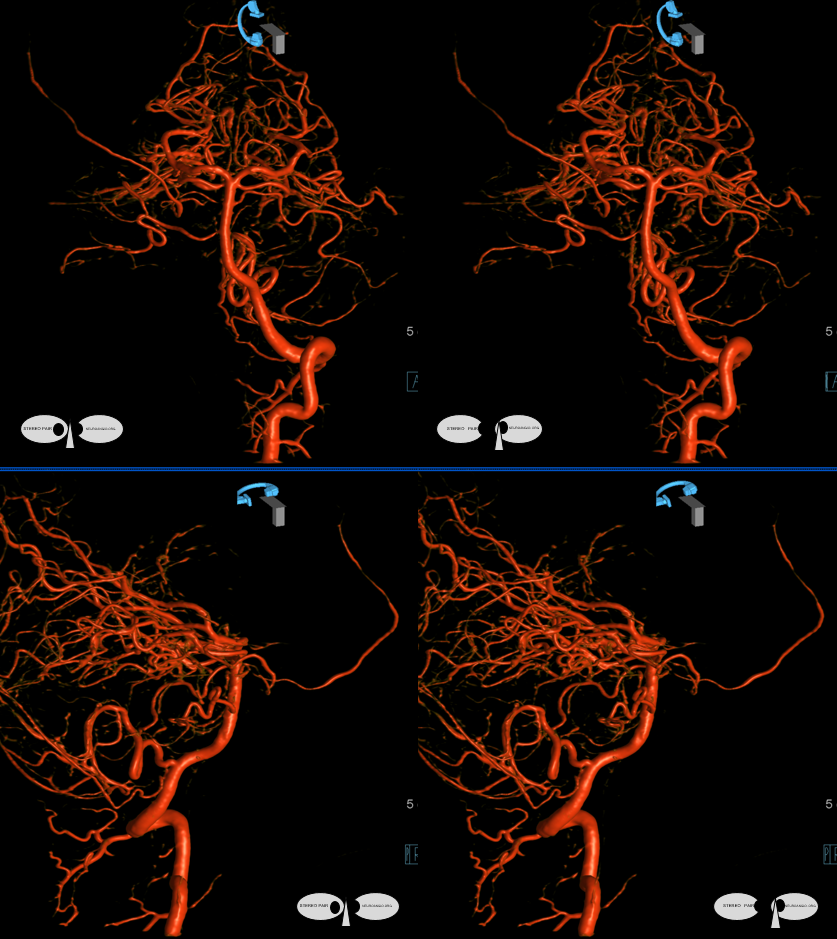

Trigeminal artery origin of the Middle Meningeal Artery — it all makes embryologic sense — check out MMA page

ECA with missing frontal division of MMA — petrosquamosal branch is shown by dashed arrows

Vert

Rotational angio and 3D MIPs

Stereo Volume Rendered images

Anaglyph stereos